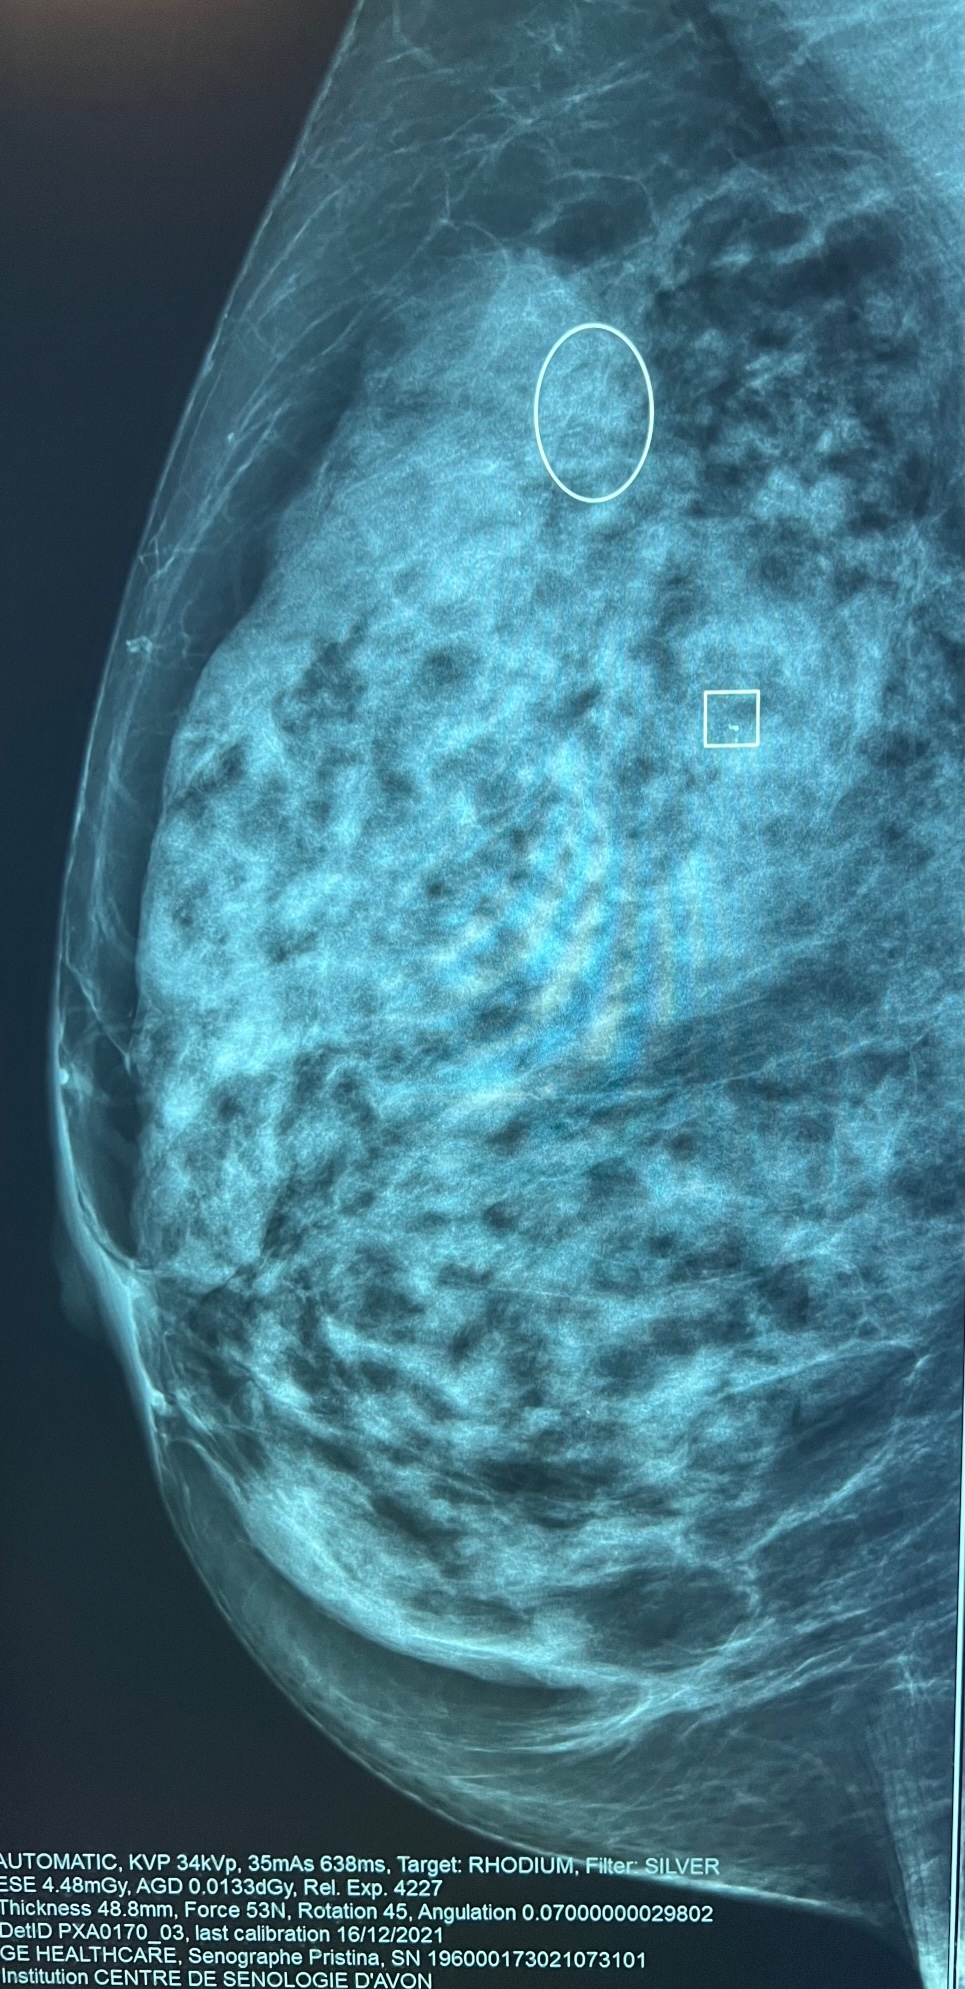

C'est un outil informatique sophistiqué complémentaire à la mammographie qui met en évidence les régions suspectes de l'image afin d'aider le médecin à détecter précocement une anomalie.

Le radiologue lit votre mammographie et dans un second temps utilise sur le mammographie numérique un CAD (computed aided detection), de dernière génération (ICAD pour imagerie 2D et tomosynthèse 3D) qui va marquer les micro-calcifications (marquées par un carré) et les masses (marquées par un rond) avec la valeur prédictive positve en faveur d'une lésion maligne.

Le radiologue décidera s'il existe ou non une anomalie susceptible d'être retenue comme pathologique.

Cet outil ne remplace pas le radiologue mais l'aide dans son travail surtout pour la détection des faux négatifs (image pathologique ou suspecte pouvant être ratée).

Micro-calcifications (carré) Petite masse, distorsion architecturale (rond)